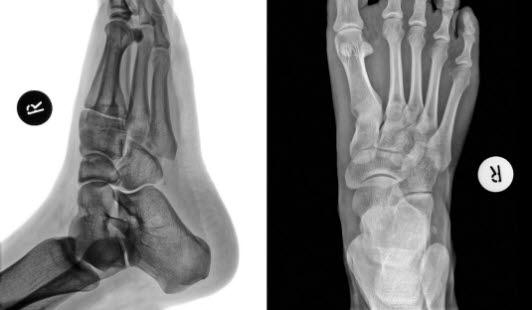

Røntgen av foten sett ovenfraFoten består av totalt 26 bein. I bakfoten finnes hælbeinet (calcaneus) og ankelbeinet (talus). I midtfoten finnes båtbeinet (naviculare), kube-beinet (cuboideum) og tre såkalte cuneiforme-bein. Fremfoten består av fem mellomfotsbein (metatarser) og 14 tåbein (falanger). Rørknokler som metatarser og falanger har en indre (proksimal) og en ytre (distal) ende. Den midtre delen er smal og lang (skaftet), og de ytre delene er fortykkede. Den proksimale enden kalles basis, og den distale benevnes caput.

Røntgen bekrefter diagnosen. Brudd i fotens metatarser og falanger kan være vanskelige å påvise hos barn pga. de mange vokstsentrene. I slike tilfeller er det nødvendig å sammenligne med bilder av den andre foten. Annen bildediagnostikk kan noen ganger være nødvendig, eks. scintigrafi, CT, MR, ultralyd.

Skaden oppstår ved fall på nedoverbøyd forfot eller slag/klemming mot forfoten. Ved undersøkelse foreligger smerter, hevelse og feilstilling av foten. Det er fare for skade på en mindre pulsåre (arteria dorsalis pedis). Brudd av basis på 2. metatars kan føre til forskyvning av de ytre metatarser (3, 4 og 5). Røntgen gir diagnosen. Siden en skade med fotroten ute av ledd ofte er kombinert med brudd, gjøres det som regel CT for å få best mulig bilder.